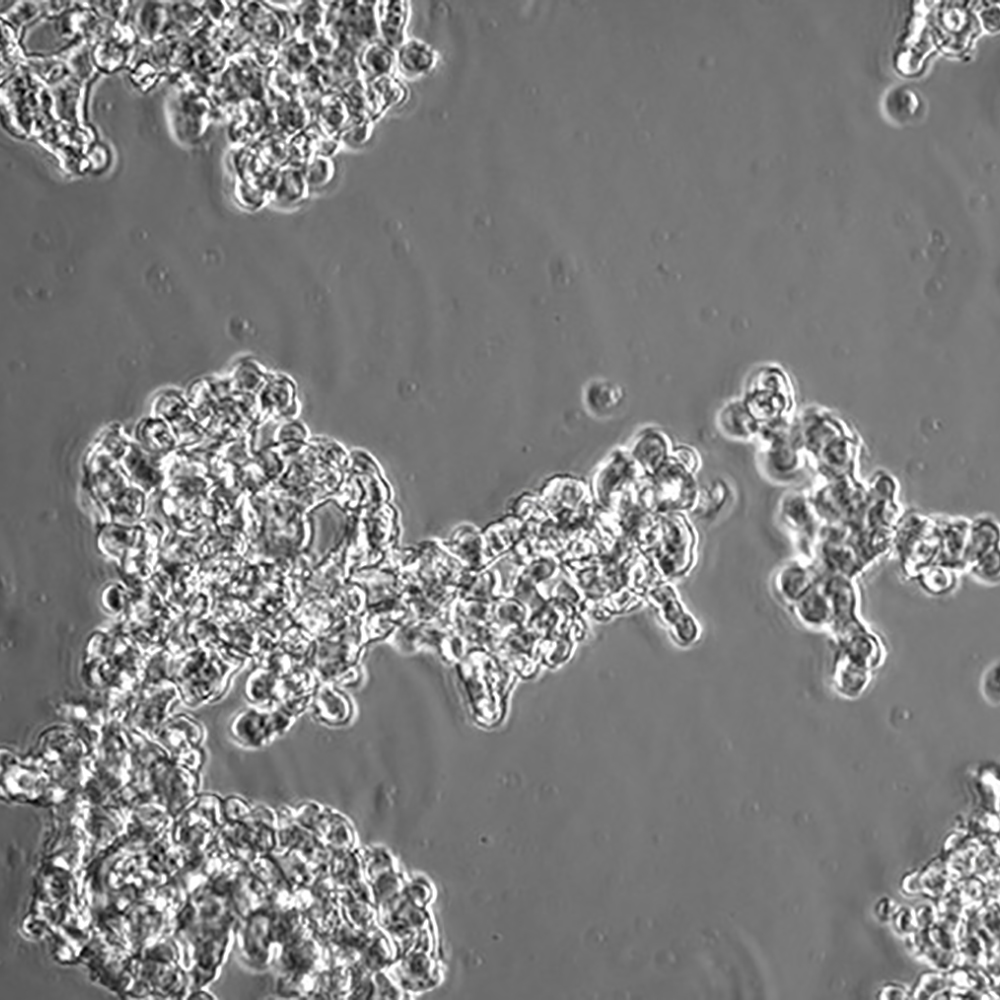

NCI-H526

產品名稱 NCI-H526

中文名稱 人小細胞肺癌細胞

組織來源 小細胞肺癌;骨髓轉移;男性

生長特性 懸浮